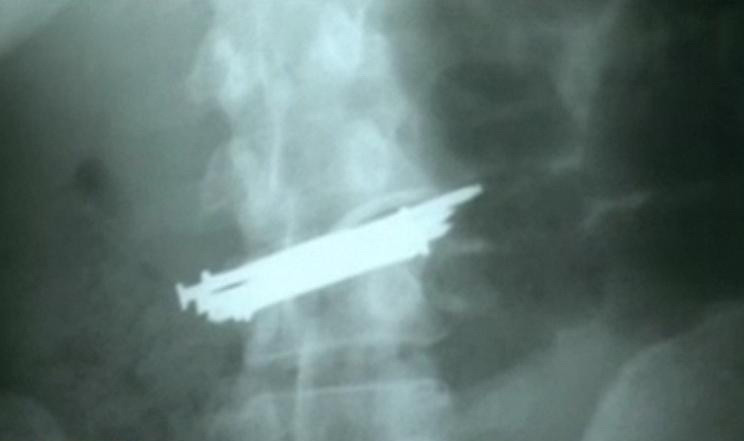

Radiografie incredibila la Lugoj. A inghitit 9 cuie si o bucata de sticla

Mai mult moarta decat vie a ajuns o tanara de 33 de ani la spitalul din Lugoj, dupa ce a inghitit noua cuie si o bucata ...